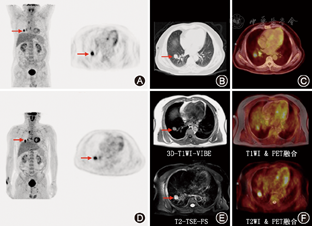

因同日显像,故不再需要18F-FDG注射。数据采集均由PET/MRI一体机(Biograph mMR, Siemens)完成:PET采集每个床位5 min,累计45 min/人。采用基于Dixon序列为基础的衰减校正方法,重建采用OSEM迭代算法,3次迭代,21个子集,高斯滤波:半高宽4.0 mm,散射校正;MR图像采用全景矩阵线圈,覆盖躯干大部(颈部至股骨中段),应用序列包括:横轴位3D容量呼吸保持T1加权序列(3-D volumetric interpolated breath-hold T1-weighted sequence,T1WI 3D-VIBE);横轴位带抑脂技术的T2加权TSE(turbo spin echo,T2WI TSE)序列;横轴位扩散加权成像(diffusion-weighted image,DWI)。PET/MRI衰减校正后即为PETMR-AC。

选择4个生理组织/器官(包括肺部,肝脏,第3腰椎以及竖脊肌)测定SUVmax,本研究定义生理组织/器官为MRI和PET图像上均无显著异常征象[9]。4组图像,包括结构像(3D-T1-VIBE,T2-TSE-FS)和PET图像(PETAC-CT和PETAC-MR)应用工作站自带分析软件(True D; Siemens)进行融合配准。所有ROI的选择和测量均由两位医生(分别12年和5年PET/CT经验、2年和6年MR经验)共同完成:直径1.5 cm圆形ROI置于右肺上叶(主动脉弓顶部水平);直径2.0 cm圆形ROI置于肝右叶(第Ⅶ段);直径1.0 cm圆形ROI分别置于腰3椎体髓腔及同层竖脊肌。相同ROI也被置于双时间点PET/CT图像的肝脏及竖脊肌内。

除了肺部(r=0.44),两组SUV在肝脏、肌肉及骨骼均有良好的相关性(图1),相关系数分别为0.62、0.73和0.69。肺部、肝脏、肌肉及骨骼SUVmax-MRI均显著低于SUVmax-CT(P<0.01),分别为:0.49±0.16比0.43±0.11,2.65±0.47比2.05±0.42,0.82±0.30比0.70±0.27,2.10±0.58比1.78±0.55。